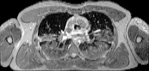

Visible Human male: Sectio transversalis 1412

CT

NMR

Pd                          / T2 \                         T1